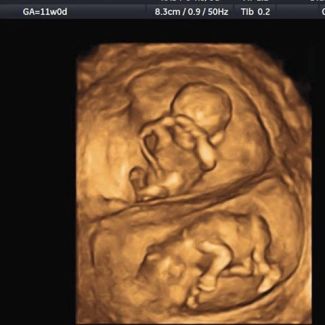

統計上

大約有三分之一到五分之一的胚胎

在12周之前

也就是三個月前

會自然淘汰掉

我趕緊幫她做了超音波檢查

還好胎兒一切正常